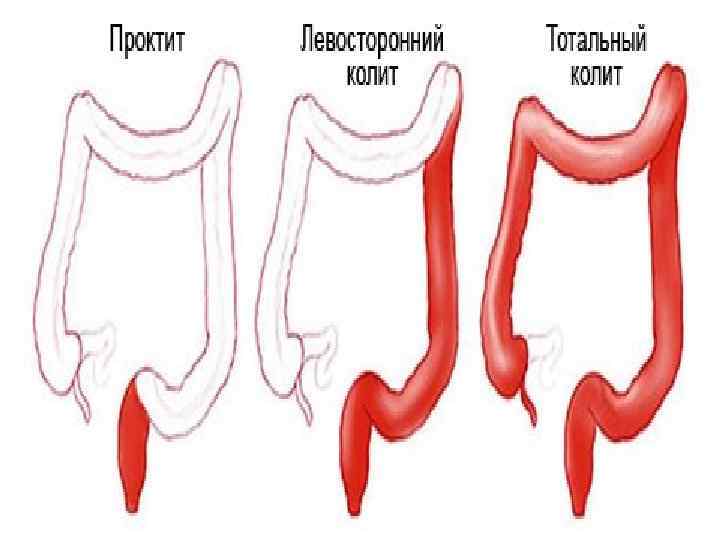

Формы язвенного колита в зависимости от локализации поражения Дистальный Левосторонний Субтотальный Тотальный

Формы язвенного колита в зависимости от локализации поражения Дистальный Левосторонний Субтотальный Тотальный